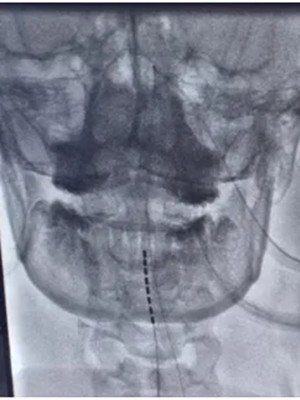

面对陈先生的病情,神经外科二病区李培栋主任、李信晓博士团队经过严谨评估,2024年8月31日,团队为陈先生实施“一体式脊髓电刺激电极植入术”。该手术仅需在颈部植入电极,手术时间短,创伤小、恢复快。

▲ 团队在患者颈部C2-C4水平硬膜外精准植入电极,并连接体外刺激器